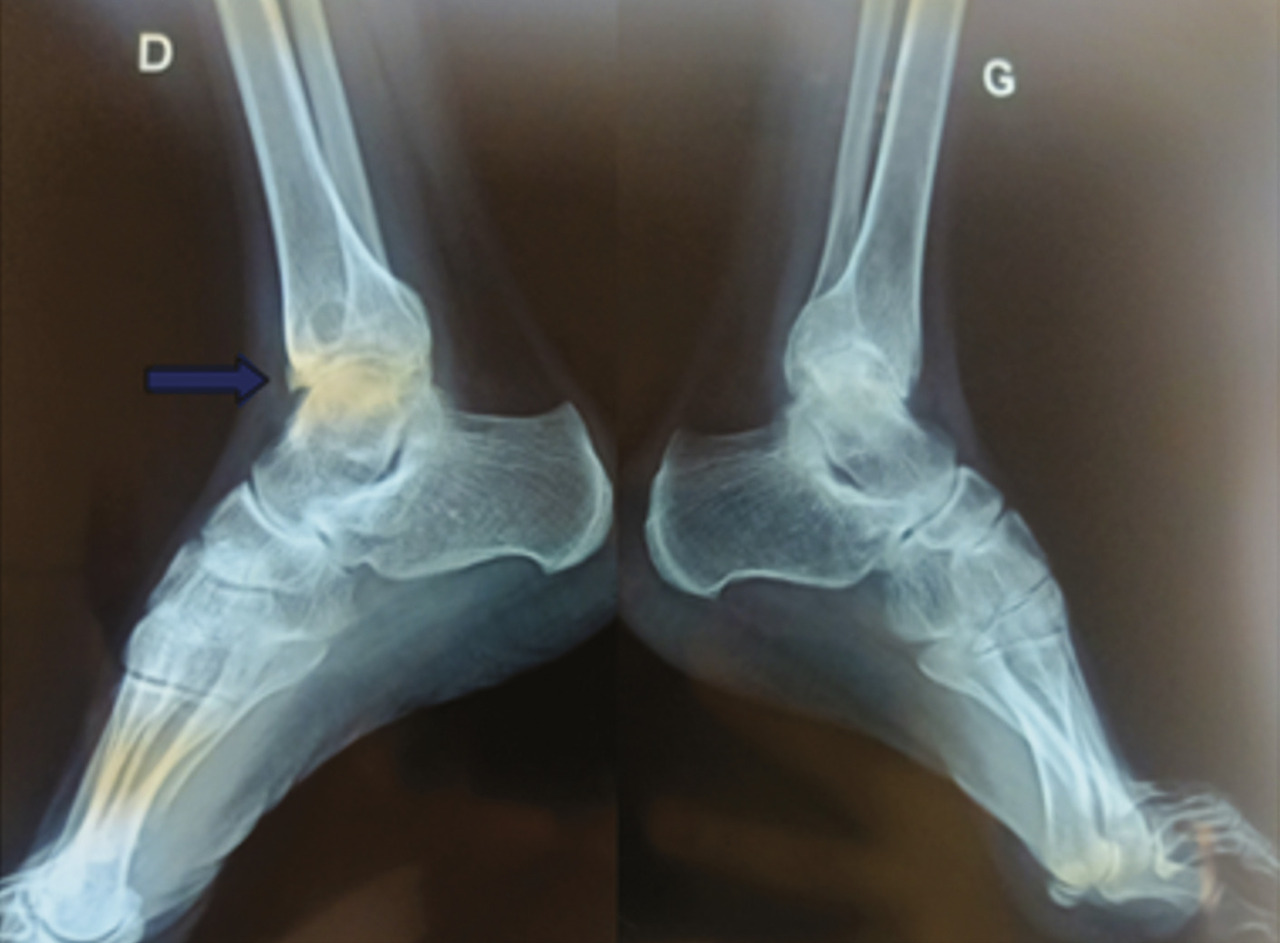

L’examen physique retrouve une hypertrophie articulaire du genou gauche avec un flessum irréductible des deux genoux, plus marqué à gauche, une atrophie du quadriceps et des muscles du mollet, une déformation avec perte de la dorsiflexion et de la flexion plantaire des chevilles (fig. 1 et 2 ). La protéine C-réactive est normale. Les radiographies des deux genoux et des deux chevilles révèlent respectivement une destruction articulaire et un ostéophyte de la partie antérieure de l’articulation talocrurale (fig. 3 et 4 ).

La radiographie standard reste l’examen de base pour rechercher des signes témoignant d’une hémarthrose et/ou d’une arthropathie hémophilique (tuméfaction synoviale, raréfaction osseuse périarticulaire, hypertrophie épiphysaire, pincement articulaire diffus, érosions marginales bien limitées, érosions et géodes centrales, stries d’arrêt de croissance, troubles de la croissance des os et déformations).6